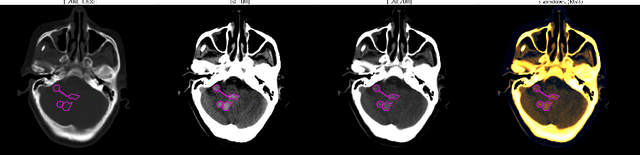

Abstract:We implemented two distinct 3-dimensional deep learning neural networks and evaluate their ability to segment intracranial hemorrhage (ICH) seen on non-contrast computed tomography (CT). One model, referred to as "Voxels-Intersecting along Orthogonal Levels of Attention U-Net" (viola-Unet), has architecture elements that are amenable to the INSTANCE 2022 Data Challenge. A second comparison model was derived from the no-new U-Net (nnU-Net). Input images and ground truth segmentation maps were used to train the two networks separately in supervised manner; validation data were subsequently used for semi-supervised training. Model predictions were compared during 5-fold cross validation. The viola-Unet outperformed the comparison network on two out of four performance metrics (i.e., NSD and RVD). An ensemble model that combined viola-Unet and nnU-Net networks had the highest performance for DSC and HD. We demonstrate there were ICH segmentation performance benefits associated with a 3D U-Net efficiently incorporates spatially orthogonal features during the decoding branch of the U-Net. The code base, pretrained weights, and docker image of the viola-Unet AI tool will be publicly available at https://github.com/samleoqh/Viola-Unet .